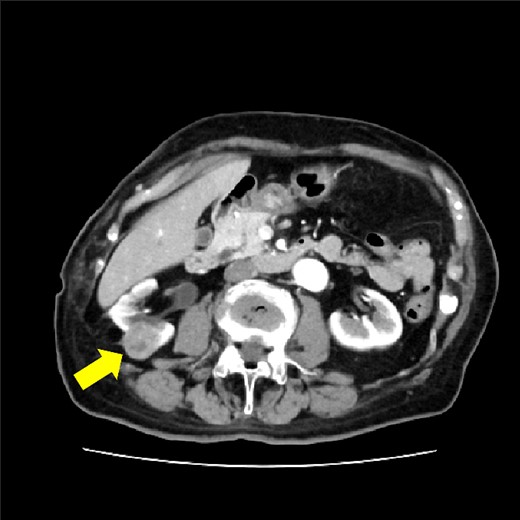

The drain was removed on postoperative day 2. On the night of the third postoperative day, the patient vomited. On the morning of the fourth postoperative day, mild abdominal pain and a ping-pong ball-sized bulge and induration were found near the surgical scar of the 5 mm port where the drain had been placed. CT confirmed an incarcerated small intestine and ileus in the 5 mm port scar where the drain had been placed (Fig. 2). Ileus removal was performed on the same day. First, the dilated wound for nephrectomy was opened, and the inside of the abdominal cavity was observed. A hanging small intestine was observed just below the 5 mm port (Fig. 3). Since it could not be conquered manually, a 2 cm vertical incision was made on the 5 mm port wound. The small intestine penetrated the anterior layer of the rectus abdominis muscle, so the fascia was carefully incised to avoid damaging the small intestine. The small intestine was returned to the abdominal cavity. The small intestine was slightly discolored (Fig. 4), but after discussion with the gastrointestinal surgeon, it was determined that it was not necrotic. No small intestine resection was performed. The wound was carefully closed using fascial sutures to prevent recurrence. The fascia was weak, likely because this patient was taking steroids. The ileus has not recurred since then. The pathological results indicated a maximum diameter of 30 mm, consistent with papillary renal cell carcinoma, classified as pT1a G3 > G2, with negative margins.

CT showing small intestine penetrating fascia of rectus abdominis. The arrow shows the incarcerated small intestine.